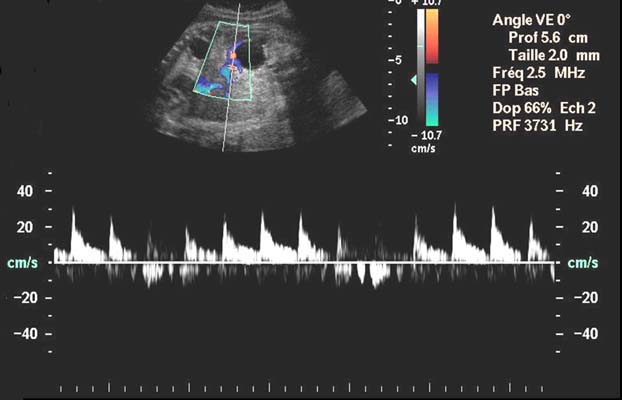

Sgtaire, VS : 25 cm/s